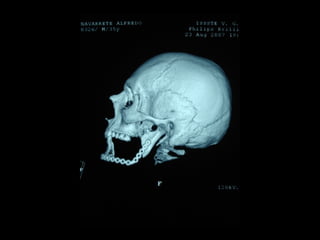

Tomografía computarizada

De seno maxilar corte sagital.

Area de implantación

Dentaria.

Tomografía computarizada De senomaxilar corte sagital. Area de implantación Dentaria.